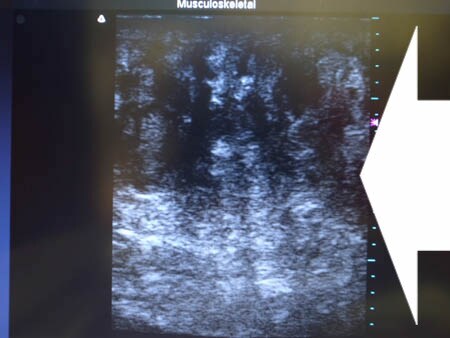

いつものように3Dタッチビュー(超音波)で

皮下脂肪層を評価してみましょう。

上腹部

いかがでしょうか?

外見上では判断できない

体内の皮下脂肪層を

3Dタッチビューでしっかりと見て

皮下脂肪の取り残しがないか?

皮下脂肪の取りむらはないか?

チェックすることは

非常に大切だと思いますし

また手術が終了した時点で

確実な結果を患者様にお約束でき

さらに患者様にもこの画像を見ていただけば

非常に満足度の高い手術になります。

今回も患者様は術中にこの画像を見て

非常に満足されていました!